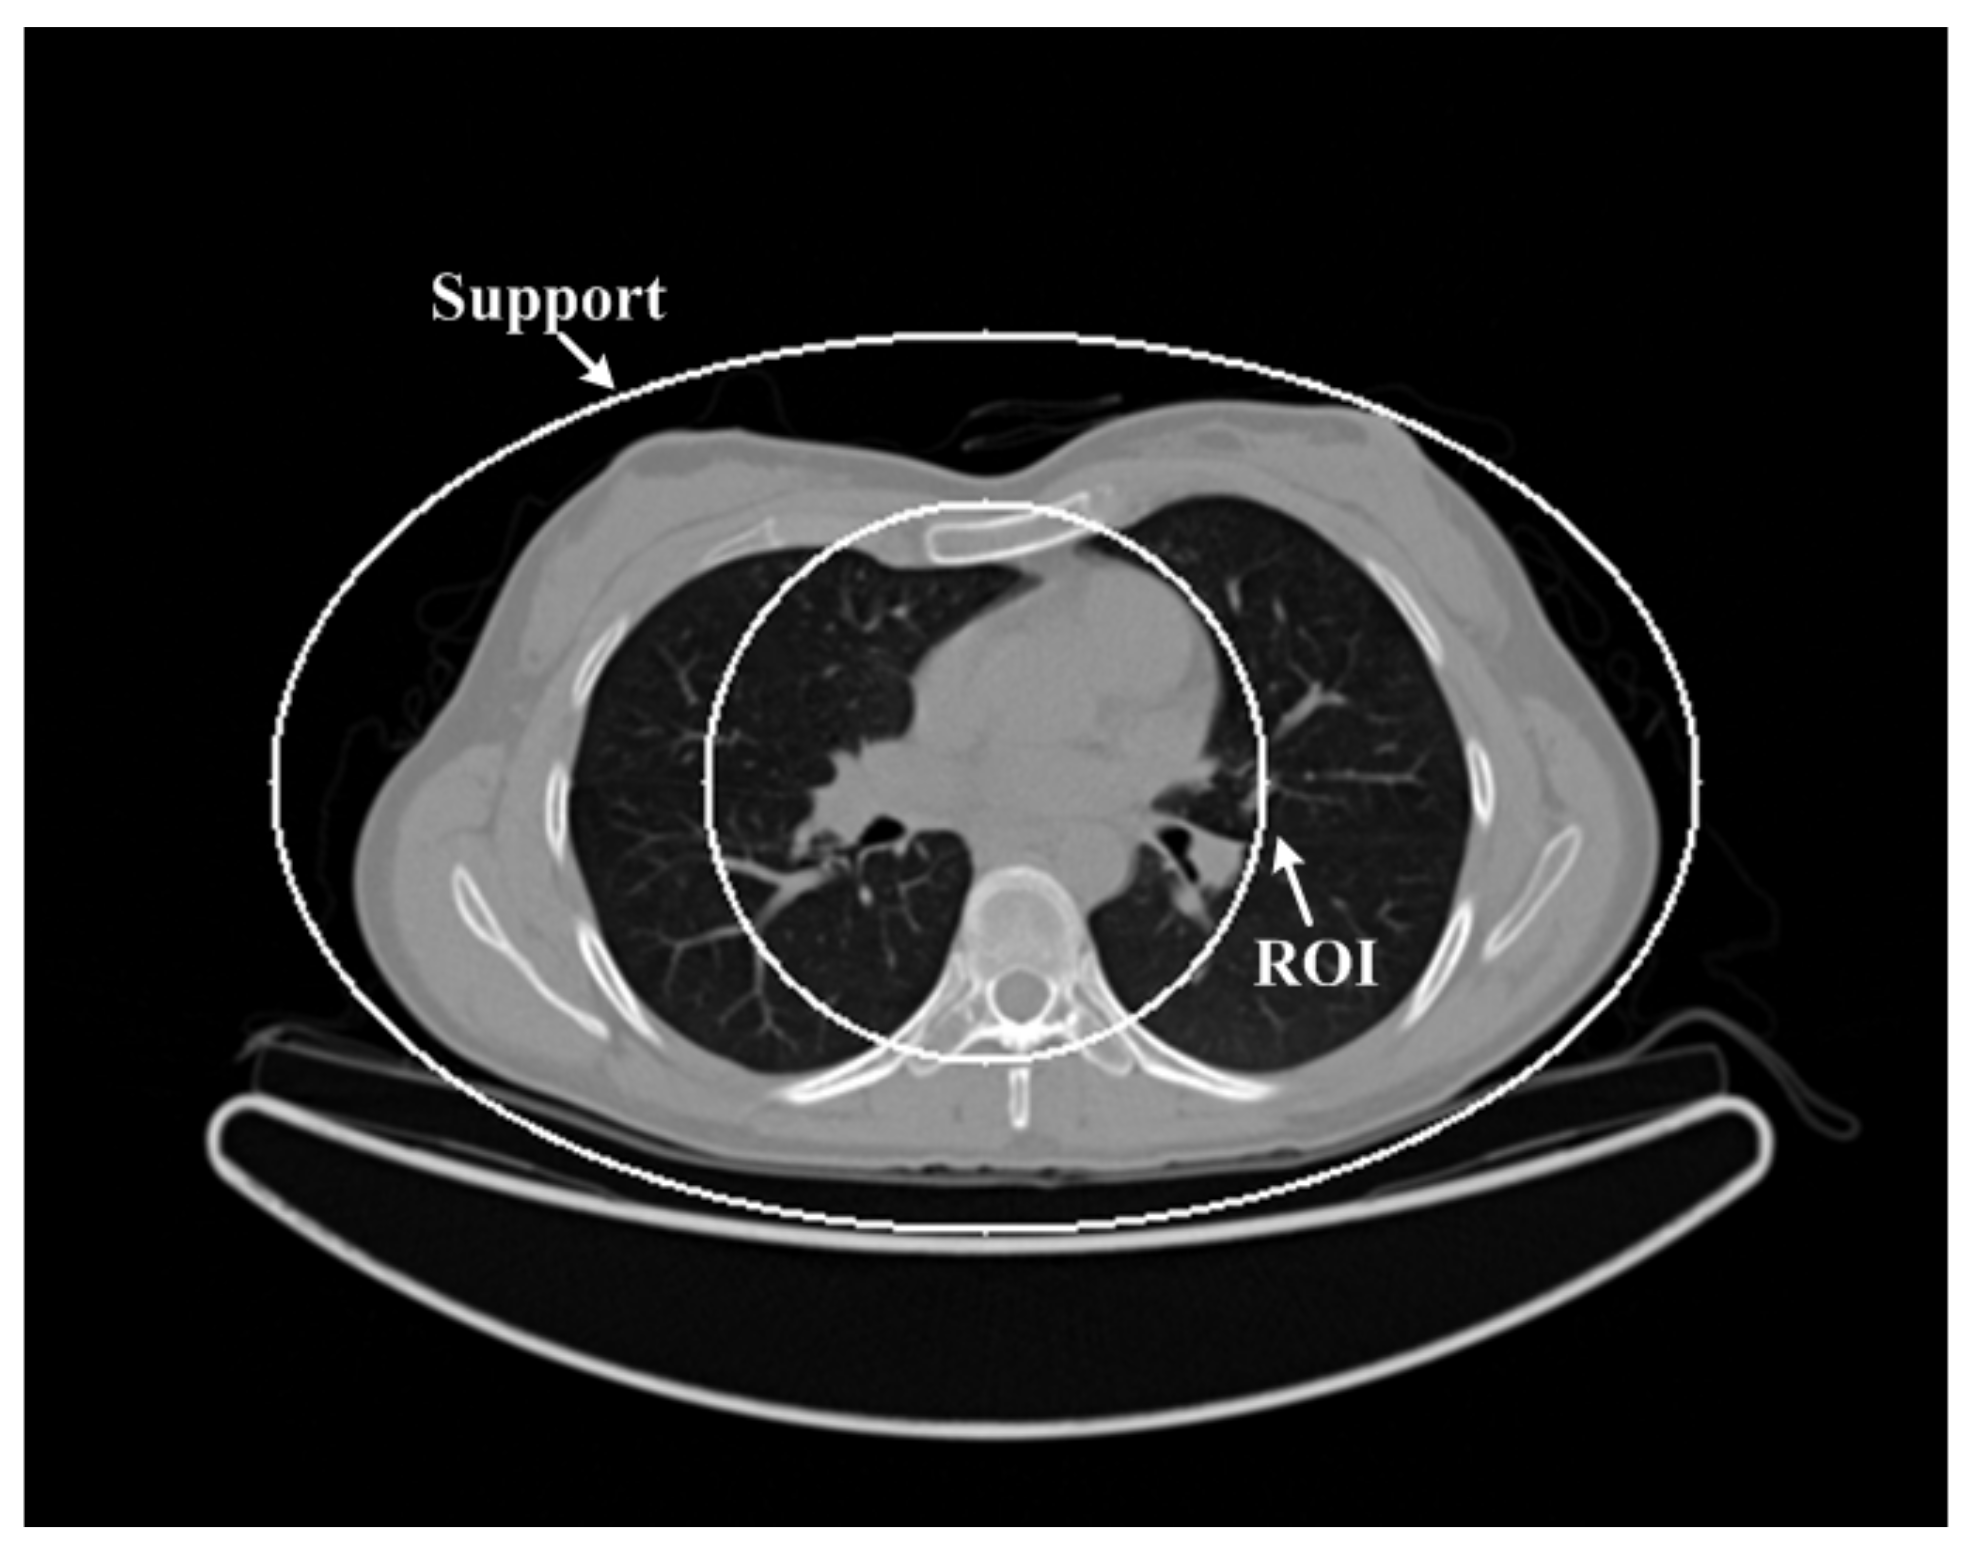

A human chest image [28] was downloaded from the website (http://wiki.kek.jp/pages/viewpage.action?pageId=13667347 accessed on 10 May 2021) to verify the performance of the above five different reconstruction algorithms. In this study, we used the downloaded chest image, which is given in Figure 1, as the ground truth. The size of the chest CT image was 512 × 512 pixels and the real size of each pixel was 0.9766 mm × 0.9766 mm. The equi-angular fan-beam uniformly collected the projection data of 360 views that only passed through the ROI region under the circular trajectory of 360°. The distances from the X-ray source to the rotation center and the detector were 570 mm and 1140 mm, respectively. In order to simulate low-dose projection data, Poisson noise with the photon numbers of Np = 1 × 105, Np = 5 × 104 and Np = 1 × 104 was added to the ideal projection data to obtain three groups of low-dose projection data. The chest image, object support and ROI are shown in Figure 1.

Figure 1.

The chest image. The display window is [−1000 900]HU.